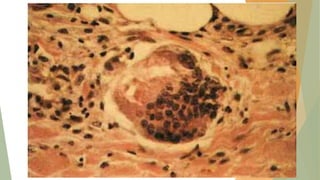

Inflamación granulomatosa

ENFERMEDADES CON INFLAMACIÓN GRANULOMATOSA

ENFERMEDAD CAUSA REACCIÓN TISULAR

TBC Mycobacterium tuberculosis

Tubérculo caseoso y no caseoso .

Focos de células epitelioides

Lepra Mycobacterium leprae

BAAR en macrófagos, granulomas no

caseosos

Sífilis Treponema pallidum Goma

Enfermedad por arañazo de gato Bacilos gramnegativos

Granuloma redondeado o estrellado

con PMN. Infrecuentes células

gigantes

Sarcoidosis Etiología desconocida Granulomas no caseificantes

Enfermedad de Crohn

Reacción inmunitaria a células

intestinales

Ocasionales granulomas no

caseificantes

Morfología

Inflamación granulomatosa ENFERMEDADES CONINFLAMACIÓN GRANULOMATOSA ENFERMEDAD CAUSA REACCIÓN TISULAR TBC Mycobacterium tuberculosis Tubérculo caseoso y no caseoso . Focos de células epitelioides Lepra Mycobacterium leprae BAAR en macrófagos, granulomas no caseosos Sífilis Treponema pallidum Goma Enfermedad por arañazo de gato Bacilos gramnegativos Granuloma redondeado o estrellado con PMN. Infrecuentes células gigantes Sarcoidosis Etiología desconocida Granulomas no caseificantes Enfermedad de Crohn Reacción inmunitaria a células intestinales Ocasionales granulomas no caseificantes